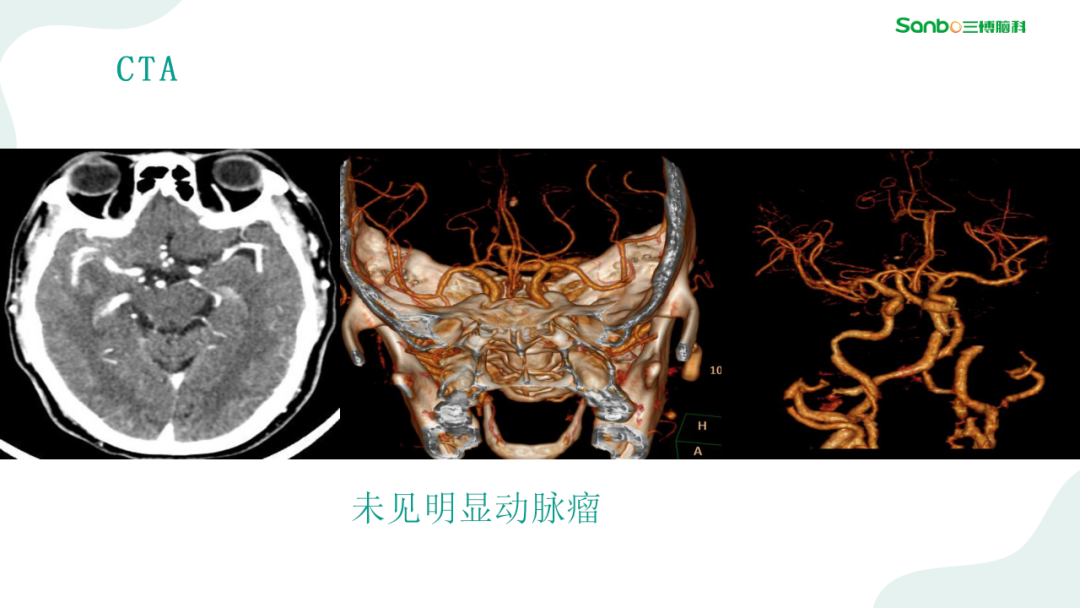

2月28日下午3:00,第二期“健康小课堂”科普活动由神外二科副主任杨海洋围绕《脑血管病的那些事》,给大家耐心讲解了有关脑血管的相关知识,生动的讲课引发在场的热烈讨论,大家纷纷表示受益匪浅。